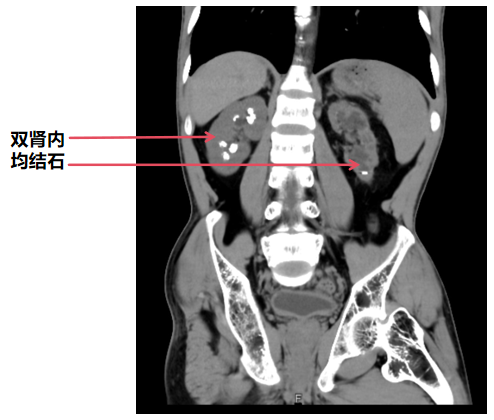

据悉,患者小张今年27岁,此前曾在当地县人民医院就诊,被确诊为“双侧肾多发结石并积水”,在当地治疗无果后,慕名求助于贵阳市第四人民医院泌尿外科何江波主任团队。不同于普通患者,小张的病情更为特殊:其7岁时便被确诊为佝偻病,双下肢呈X型腿,双侧髋关节活动障碍,后续因下肢严重畸形接受过手术治疗。这一特殊病史,不仅给手术体位的布置带来极大不便,也让术后护理工作难度陡增;加之小张同时存在脊柱侧弯、腹腔脏器解剖结构位移等问题,进一步提升了手术及麻醉的风险。

在确认小张麻醉平稳后,何江波主任立即开展手术。当输尿管软镜进入小张肾盂内时,现场医护人员均倍感意外——小张的结石并非生长在常规的肾盏内,而是位于黏膜下,且肾盂肾盏已被结石压迫变形,完全失去原有正常结构,这无疑让本就复杂的手术难度再上一个台阶。